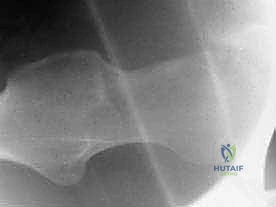

- الأشعة السينية (X-rays): لتقييم شكل العظام، قياس "زاوية ألفا" (Alpha Angle)، وتحديد وجود نتوءات الكامة أو الكماشة.

- الرنين المغناطيسي (MRI) أو أشعة الرنين بالصبغة (MRA): وهو الفحص الذهبي لرؤية الأنسجة الرخوة وتقييم تمزقات الشفا الحقي وتلف الغضروف بدقة متناهية.

- الأشعة المقطعية الثلاثية الأبعاد (3D CT Scan): للتخطيط الجراحي الدقيق قبل العملية.